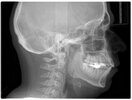

Hey guys, I’m new here so sorry if I sound dumb, just trying to learn. I’m 25 and really insecure about my side profile. My bite’s fine but my chin looks weak and kinda tucked back, with a small pouch of fat under it.

Would losing weight help or is it more of a chin/jaw issue that needs surgery like genio or LJS/DJS? I’d appreciate any honest advice or similar experiences.

i think you might need jaw advancement, genio would help since your frankfurt plane is recessed but bimax would be best